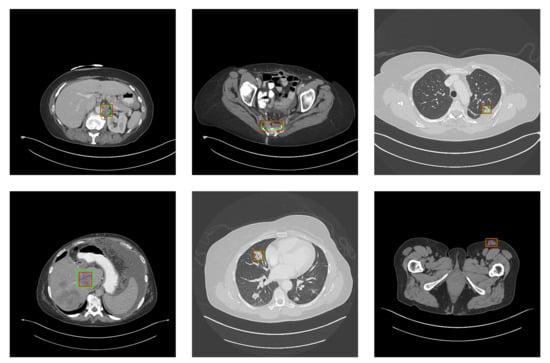

5.2. Detection Results

For further comparison, we extracted six images from the CT image series of DeepLesion. These images were taken from different sites of lesions and different areas of lesions, showing the detection results of the comparison model as comprehensively as possible. Figure 10, Figure 11, Figure 12, Figure 13, Figure 14, Figure 15, Figure 16, Figure 17, Figure 18 and Figure 19 show the detection results. All green boxes represent ground truth; red boxes denote predicted bounding boxes. It can be seen that Faster-RCNN performs very poorly on small lesions and lesions that are not easy to identify, while YOLO v3, YOLO v4, and SSD series perform relatively well. However, the aspect regression of the bounding box at small lesion locations is still not accurate. On the other hand, EfficientDet, Mask-RCNN, and YOLO v5 perform relatively well and detect lesions accurately. This may be related to the attention extraction module in these networks.

Figure 11.

The detection results of YOLO v4 in the DeepLesion dataset. The green box marks the location of the lesion.